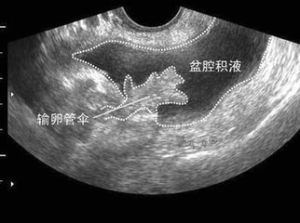

4、超聲檢查方便快捷,在盆腔積液檢查中對疾病的明確診斷方面有著明顯的優越性。相對於其他檢查診斷方法,超聲作為一種無創、無痛、方便的檢查手段,對各種原因引起的盆腔積液,可以根據超聲檢查,同時結合臨床資料及實驗室檢查,在明確診斷方面有著明顯的優越性。

5、彩超檢查,確定有無盆腔積液,進行彩超檢查是的檢查方法。可快速準確確定積液的量。

盆腔積液的位置多發生在子宮直腸陷窩等盆腔內位置較低處,婦科常用的有效檢查手段是B超,可以較準確的判斷積液的量。